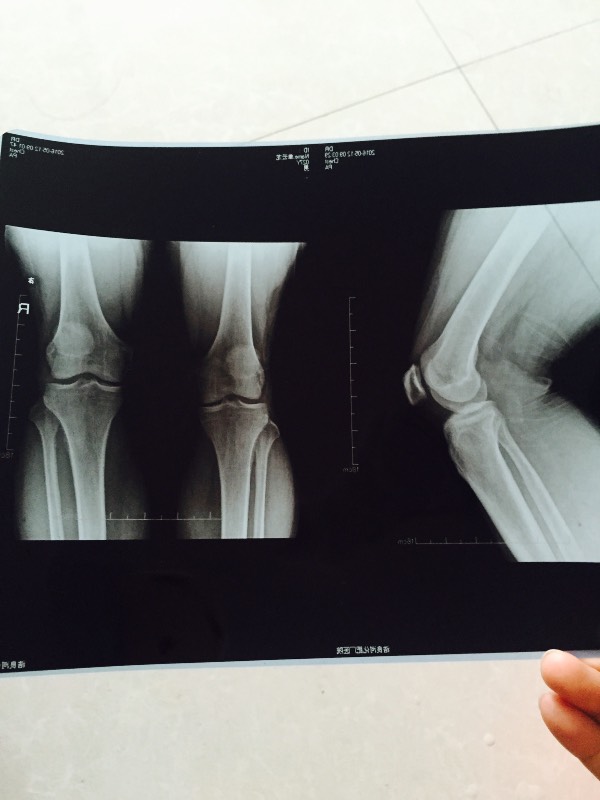

我弟弟腿部关节疼痛,在医院拍片了,医生也没说啥问题.请大家帮我看